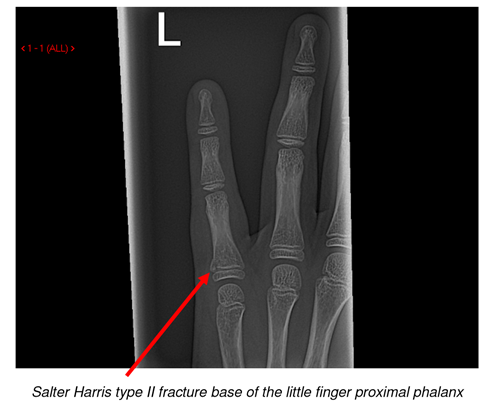

In a comprehensive examination of the 1998 National Hospital Ambulatory Medical Care Survey from US facilities, Chung et al. 3,4 In the UK, a stratified examination found the number of hand fractures per year within the general pediatric population to be low in toddlers (34/100,000 children), and increased nearly 20-fold after the 10th year to 663 hand fractures each year per 100,000 children ages 11-18. 1, 2 In the pediatric population, hand fractures make up 2.3% of all ER visits, and the incidence of these fractures varies significantly by age. Population database studies often use 18 years as a cut-off age for defining these fractures and may overestimate the prevalence of true pediatric hand fractures.įifteen percent of all fractures seen in the ER setting are hand fractures and nearly half of these fractures are a result either of sports activities or fights. Typically, a “pediatric” hand fracture would include children who continue to have open physes and therefore deserve special consideration regarding immobilization, remodeling potential, and surgical indications. Despite the high potential for excellent outcomes in pediatric hand fractures, some fractures remain difficult to diagnose and treat.ĭistinguishing true “pediatric” hand fractures from fractures occurring in skeletally immature children and adolescents can be difficult if using epidemiologic studies only. Following immobilization, children rarely develop hand stiffness and formal occupational therapy is usually not necessary. Most fractures complete bony healing in 3-4 weeks, with the scaphoid being a notable exception. In children, the thick, vascular-rich periosteum and bony remodeling potential make anatomic reductions and internal fixation rarely necessary. Most fractures can be treated operatively with closed reduction and percutaneous pinning if addressed within the first week following the injury. However, fractures may require operative stabilization if they have substantial angulation or rotation, extend into the joint, or cannot be held in a reduced position with splinting alone. If correctly diagnosed, reduced and immobilized, these fractures usually result in excellent clinical outcomes. Most simple fractures can be treated with appropriate immobilization through buddy taping, finger splints, or casting. Identification of the fractures in the emergency room setting can be challenging owing to the physes and incomplete ossification of the carpus that are not revealed in the xrays. Pediatric hand fractures are common childhood injuries.